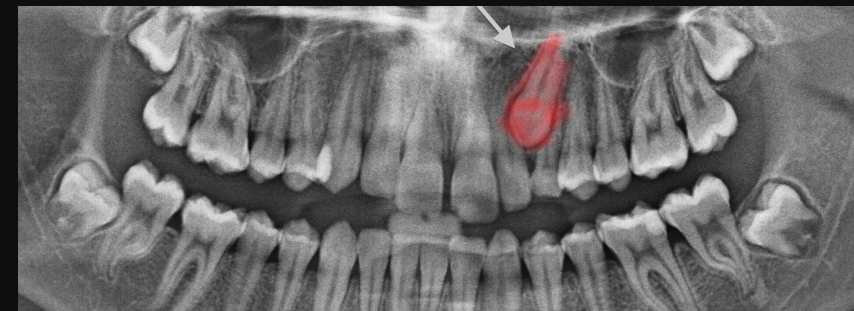

בדיקות הדמיה לצורך אבחנה

הכלי המרכזי לאבחון שן כלואה הוא צילום פנורמי, צילום רחב של כל הפה והלסתות, שמאפשר לזהות מיקום, מנח וזווית של שיניים שלא בקעו. במקרים מורכבים, במיוחד כאשר קיים חשש לקרבה לעצב (כמו בשן בינה תחתונה), ייתכן צורך גם בצילום CT דנטלי, המאפשר מבט תלת-ממדי מדויק על המבנה האנטומי.

מעבר לזיהוי עצם קיומה של שן כלואה, לצילומי ההדמיה יש תפקיד מרכזי בקבלת ההחלטה הטיפולית. באמצעות צילום פנורמי ולעיתים גם CT דנטלי תלת ממדי, אפשר להעריך לא רק את מיקום השן, אלא גם את דרגת הכליאה שלה, כיוון הצמיחה, עומק החדירה לעצם והקרבה למבנים אנטומיים רגישים כמו תעלת העצב בלסת התחתונה או הסינוסים בלסת העליונה.

נתונים אלו מאפשרים לרופא לקבוע האם קיימת אפשרות למעקב בלבד, או שקיים סיכון ממשי שמצדיק טיפול כירורגי יזום. בנוסף, הם משמשים לתכנון מדויק של ההליך, להפחתת סיכונים ולבחירת שיטת הטיפול הבטוחה ביותר עבור כל מטופל ומטופלת.